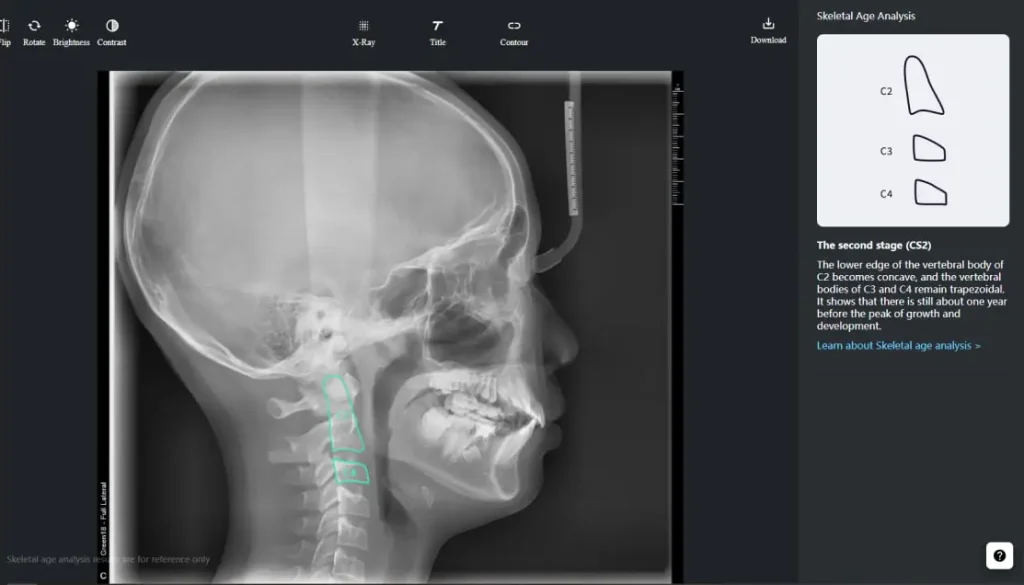

Intelligent Cephalometry System

Intelligent Cephalometry System (ICS) :

- • Tracing based on AI

- • Superimposition

- • Skeletal age analysis based on AI